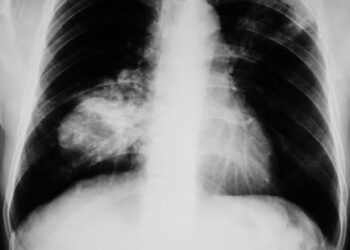

Llamamiento a mejorar la detección temprana del cáncer de pulmón en mujeres

La doctora Dolores Isla, presidenta de ICAPEM y jefa de Oncología Médica en el Hospital Lozano Blesa, ha destacado la necesidad de mejorar la detección temprana del cáncer de pulmón en mujeres. Este llamamiento se realizó durante un evento coorganizado por ICAPEM y la Asociación Española de Afectados por Cáncer...`>